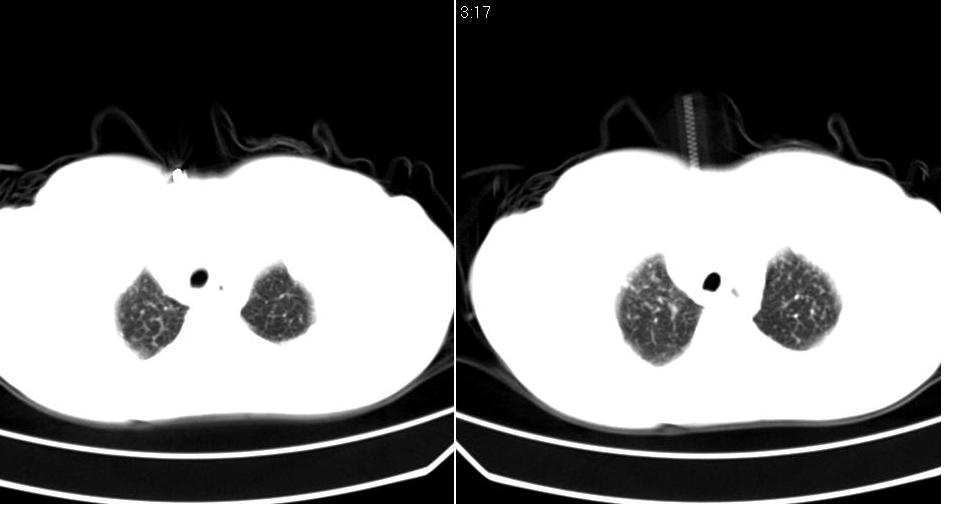

标题: CT16839:胸部CT平扫

女 50岁,在其他医院确诊肺癌.

先考虑:肺癌伴肺转移。

建议:结合临床资料,或穿刺活检,除外继发性肺结核之可能。